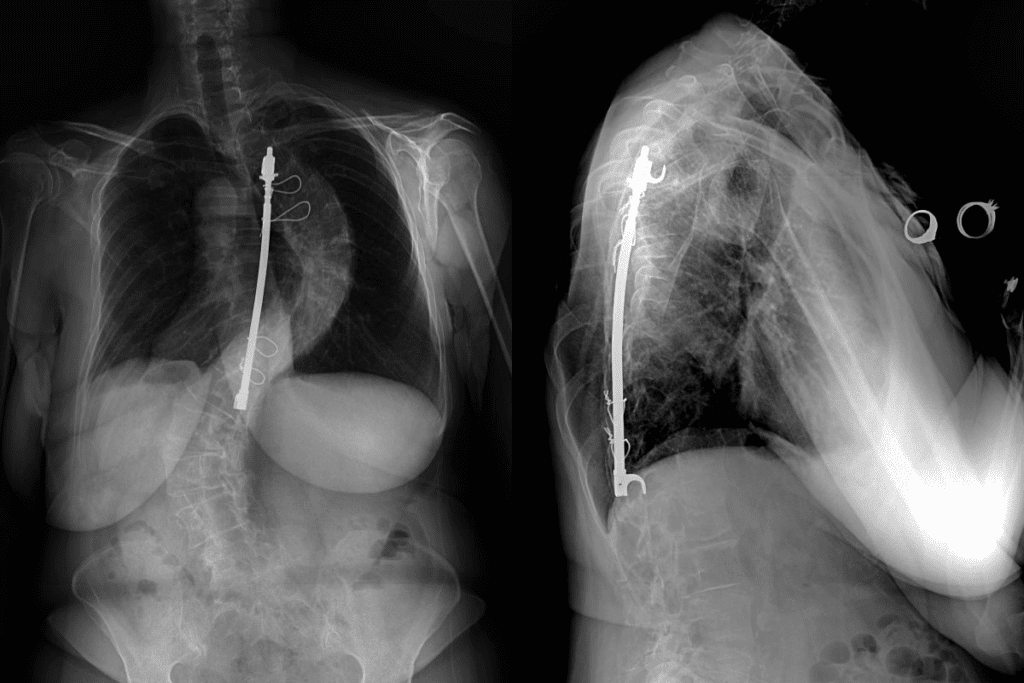

Imaging Studies for Adult Scoliosis

Imaging tests are key for diagnosing and figuring out how severe scoliosis is. The main tests are:

- X-rays: To see how curved your spine is and its alignment.

- CT scans: For detailed images of your spine, including vertebrae and discs.

- MRI scans: To see soft tissues like nerves and discs and spot any problems.

Surgical Interventions and When They’re Necessary

Surgery is usually for those with severe scoliosis or who haven’t improved with other treatments. Surgical options include:

- Spinal Fusion: This joins two or more vertebrae to stabilize the spine.